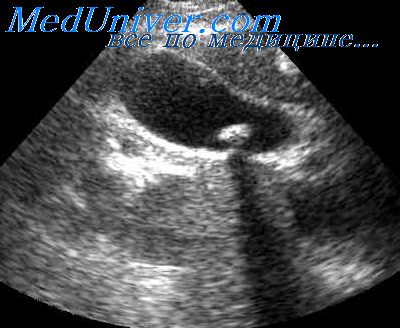

Продольный размер пузыря в норме составляет 5-7 см, толщина стенок – от 2 до 3 мм. Внутренне пространство органа содержит небольшой объем желчи с равномерной, однородной консистенцией.

Протоки, предназначенные для сообщения желчного пузыря, печени и 12-перстной кишки, многочисленны, но для диагностики важно оценить диаметр общего протока, в норме этот показатель составляет 6-9 мм. Увеличение размеров желчного пузыря может свидетельствовать об избытке в нем биологической жидкости, уменьшение – о дискинезии желчевыводящих путей в гипермоторной форме

Во время УЗИ легко обнаружить холецистит на любой стадии, так как при обследовании явно прослеживается осадок в желчи или наличие камней различных размеров.

Что касается протоков, патологическими явлениями считаются участки с расширением или сужением, а также новообразования в виде кист.

Расшифровка результатов УЗИ

Как правило, результаты полученные на УЗИ расшифровывает врач, но чтобы быть спокойным, можно разобраться заранее и самостоятельно. Для этого мы предоставим некие нормы:

- грушевидная или цилиндрическая форм органа с четкими контурами;

- ширина пузыря от 3-х до 5-ти см;

- длина от 6-ти до 10-ти см;

- его объем от 30-ти до 70-ти см3;

- стенки не превышают 4 мм;

- а поперечник долевых протоков – 3-х мм;

- а общий желчный проток (норма) от 6-ти до 8-ми мм — это нормальное состояние органа у взрослых.

Любые отклонения в ту или иную сторону говорят о патологии желчного пузыря. Например, холецистит может провоцировать утолщение стенок органа, хронический холецистит – уменьшать размеры пузыря и размывать его контуры, дискинезия желчного пузыря отражается на его форме и тонусе, а ЖКБ (калькулезный холецистит) показывает наличие конкрементов (камней) в полости.